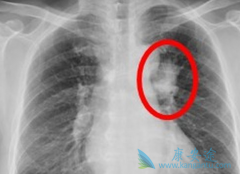

肺癌是我国乃至全球实体瘤中的常见病和高发病。很多患者认为得了肿瘤就给人生判了死刑,需要化疗就会出现不可想象的副作用。那么随着医学科技的不断进步,各类靶向药物及免疫检查点抑制剂相继问世,不仅减轻了传统化疗带给患者的痛苦、副作用,更重要的 ...

肺癌是我国常见的恶性肿瘤之一。肺癌主要分 小细胞肺癌 (SCLC)和非小细胞肺癌(NSCLC)。小细胞肺癌(SCLC)约占肺癌的15%,尽管近年来其发病率相对较低,但大部分SCLC患者发现时已处于广泛期,导致总体生存率偏低,且具有恶性度高、侵袭性强、进展较快 ...